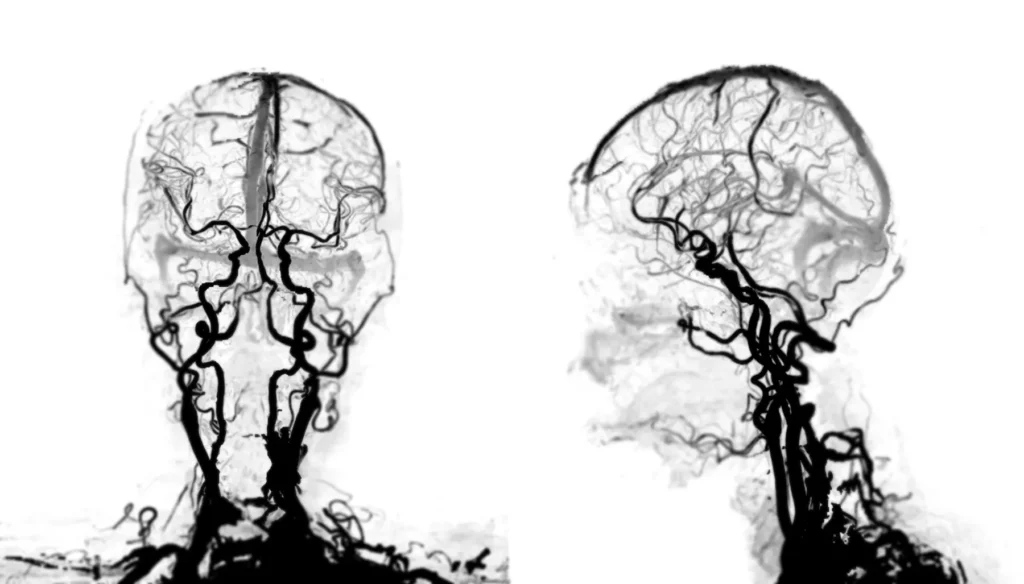

Standardul de aur pentru evaluarea non-invazivă a unei MAV, în special în afara urgenței, este rezonanța magnetică (RMN) cerebrală și angiografia prin RMN (ARM). RMN-ul oferă imagini extrem de detaliate ale țesutului cerebral, putând arăta cu precizie localizarea ghemului vascular (nidusului), efectele sale asupra creierului din jur și poate identifica semne ale unor sângerări mai vechi, minore, care ar fi putut trece neobservate. Angio-RMN-ul este o secvență specială care reconstruiește arborele vascular, oferind o hartă tridimensională a arterelor care alimentează MAV-ul și a venelor care îl drenează.

Investigația definitivă, absolut esențială pentru planificarea oricărui tratament, este angiografia cerebrală digitală cu substracție (DSA). Aceasta este o procedură invazivă, considerată standardul de aur. Se realizează într-o sală specială de angiografie, sub anestezie locală sau generală. Un cateter subțire este introdus printr-o arteră, de obicei la nivelul pumnului sau în zona inghinală, și este ghidat sub control radioscopic până la nivelul arterelor care irigă creierul. Se injectează substanță de contrast direct în aceste artere, iar un aparat digital captează imagini de înaltă rezoluție, în timp real, ale fluxului sanguin. Această investigație oferă o “hartă” dinamică și extrem de precisă a MAV-ului, arătând exact care artere îl alimentează, cât de rapid este fluxul prin nidus, dacă există anevrisme asociate (puncte de risc maxim de ruptură) și, crucial, cum și pe unde se drenează sângele venos. Această înțelegere detaliată a arhitecturii vasculare este vitală pentru ca echipa de neurochirurgie în Baia Mare să poată stabili cea mai sigură și eficientă strategie de tratament.